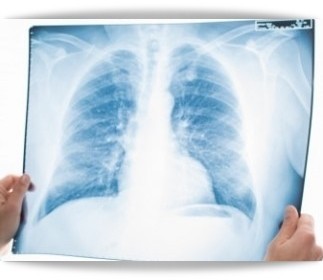

1차성 기흉은 키가 크고 마른 체격의 남성들에게 많이 나타나며, 폐의 윗부분에 있는 작은 공기주머니에 공기가 차면서 생깁니다. 주로 흡연자에게서 많이 발견되며, CT촬영을 하게 되면 대부분의 사람들이 폐에 이상을 보입니다.